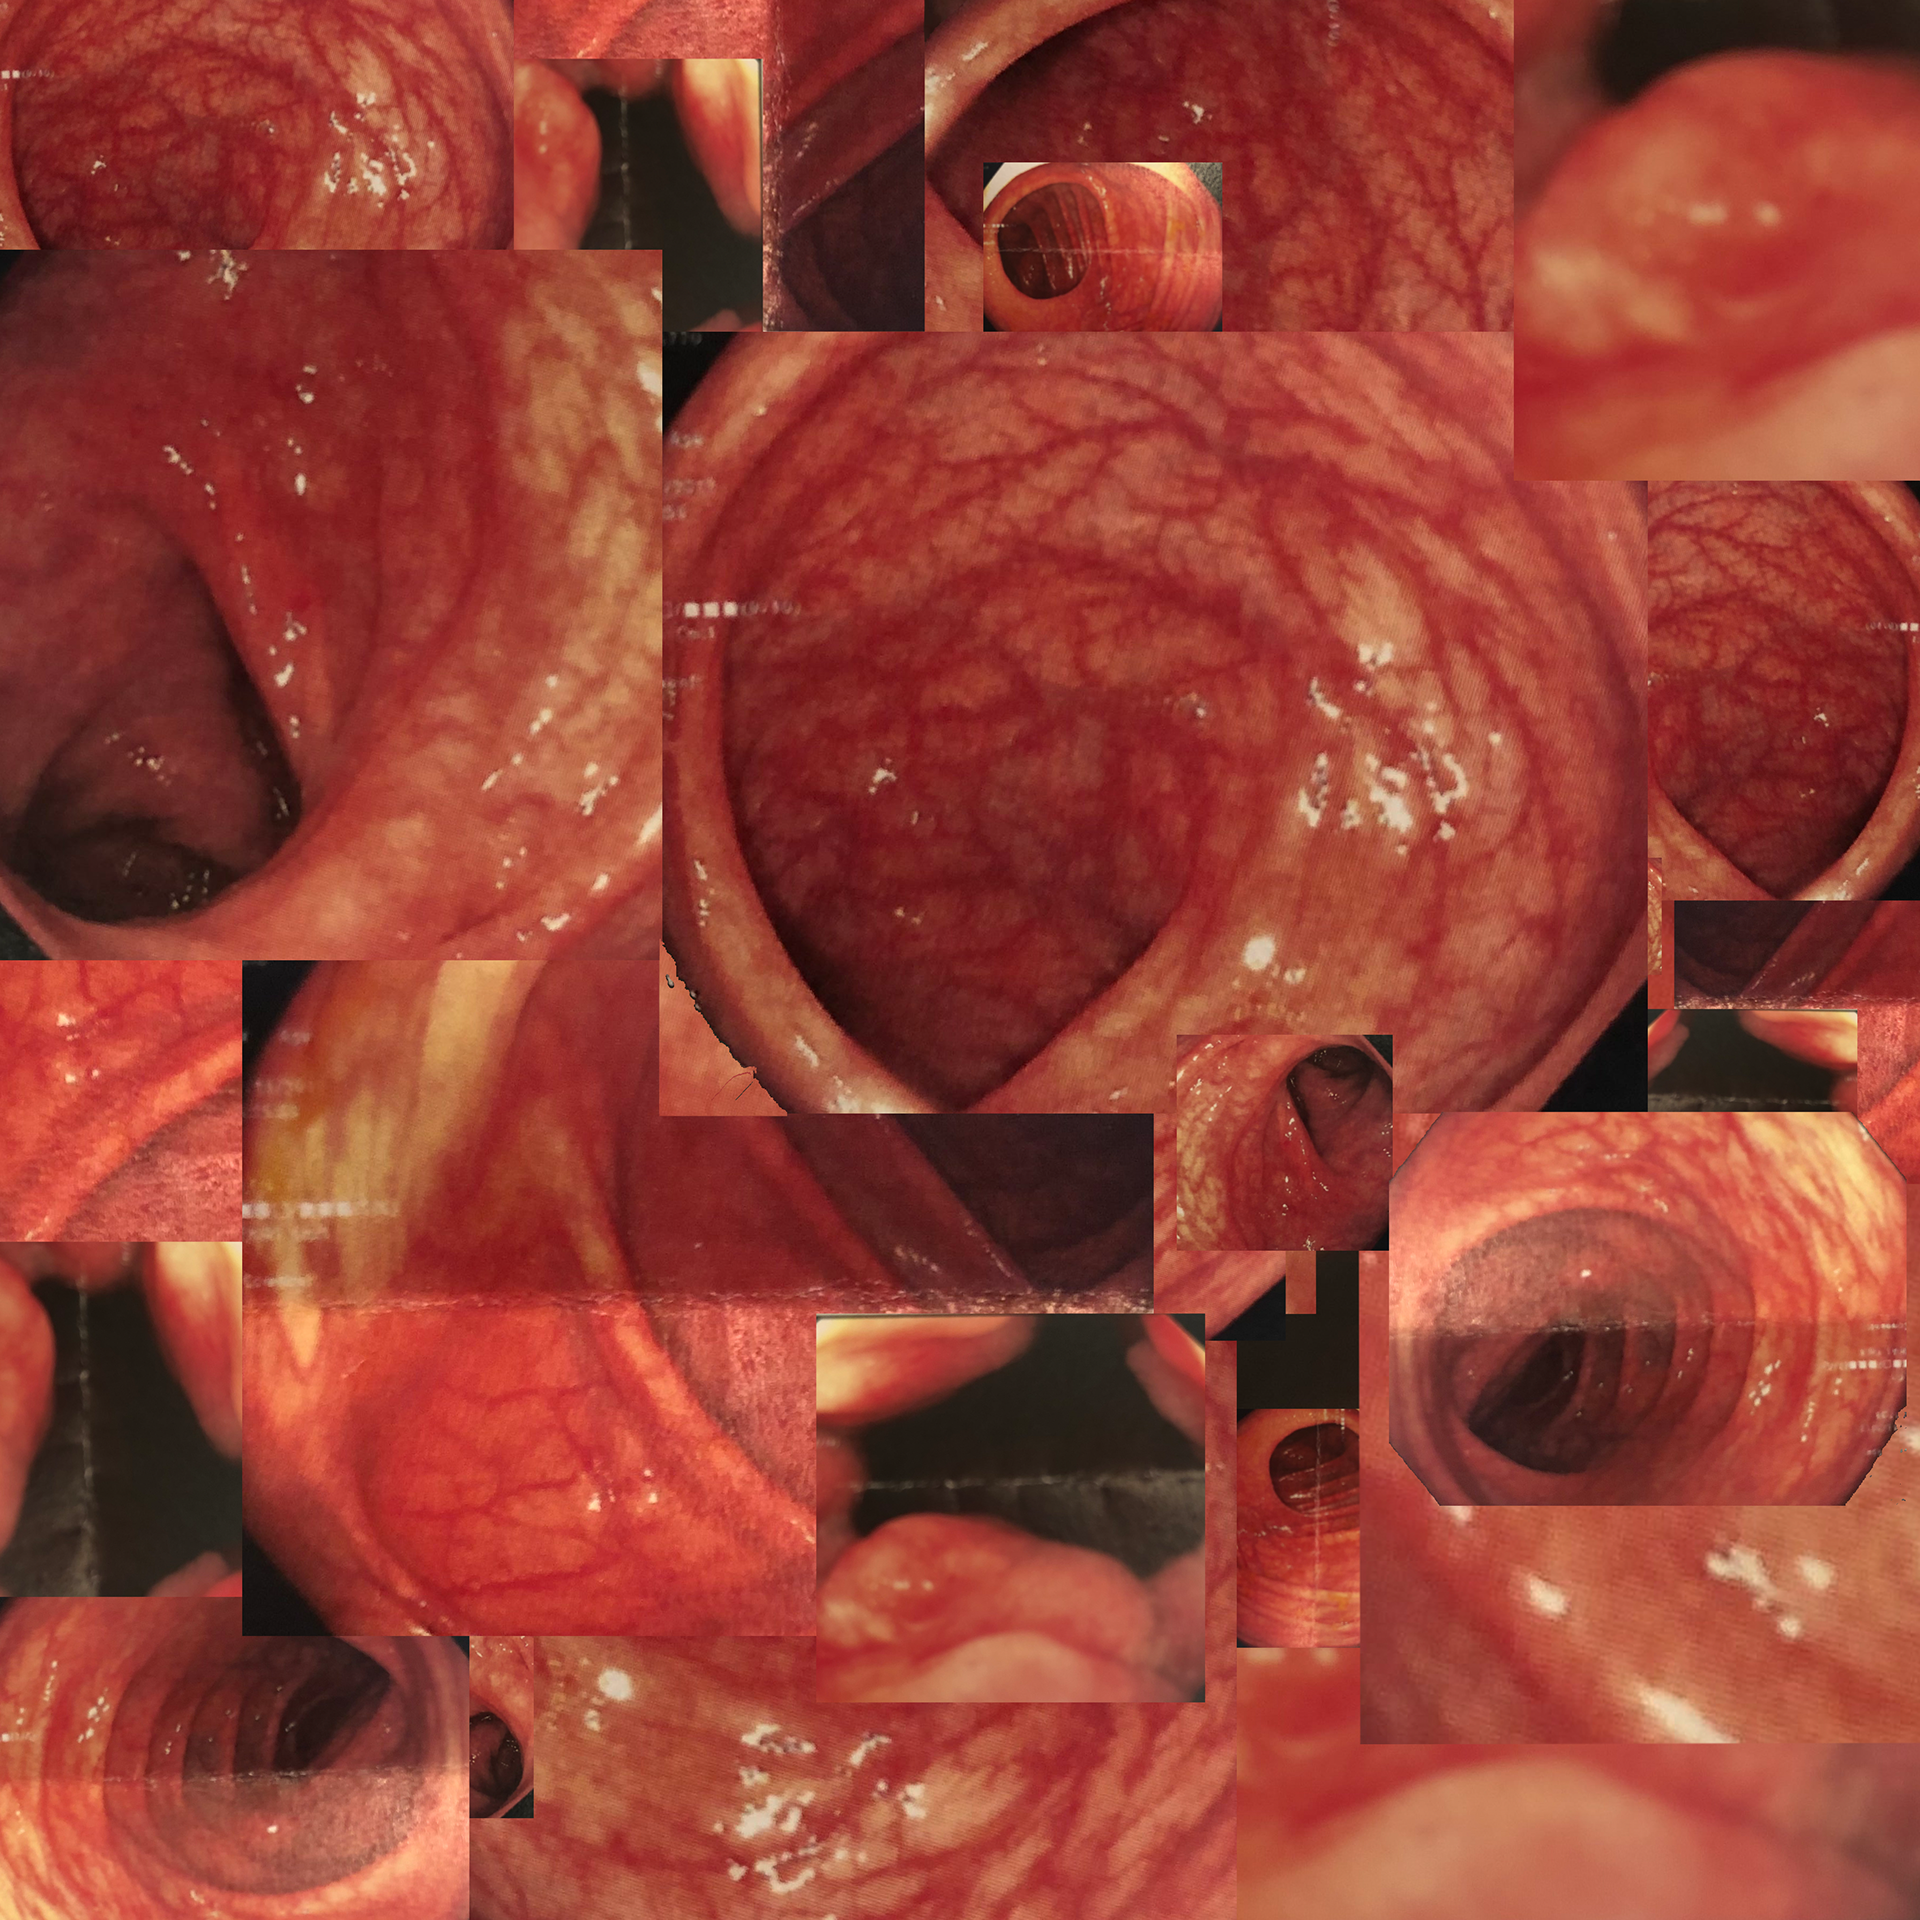

Next, I created a simple collage of photos from my colonoscopy based on Chichu's topology.

The next step was to produce a fleshed out collage (no pun intended) centered on the previous iteration. This collage was then turned to grayscale and separated by darkness into 13 layers.